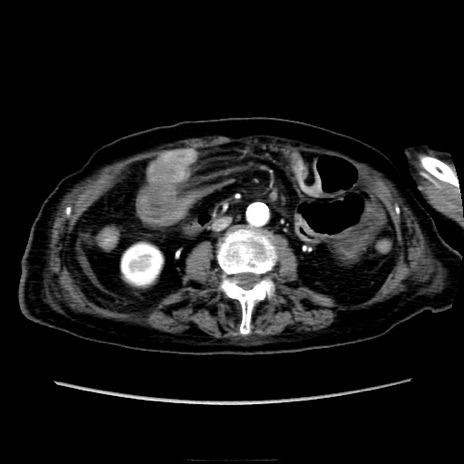

症例40(横断像)

【症例】90歳代女性

【主訴】腹痛・嘔吐

【現病歴】 食欲低下、嘔吐があり昨日他院受診。肺炎と診断され入院となる。入院後より腹部全体に圧痛あり。胃管留置され経過みていたが、症状持続するため、

当院転院となる。

【既往歴】胸椎圧迫骨折、胆石症

【身体所見】腹部:中央に激痛あり、圧痛あり、反跳痛不明

【データ】WBC 17100、CRP 18.82

横断像